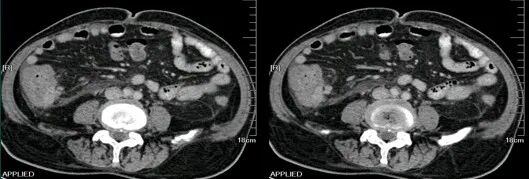

肝挫裂伤

[病因病理]

肝挫裂伤主要是指腹部受到外在力量的撞击而产生的闭合性损伤,是常见的腹部严重创伤,多由高处坠落、交通意外等引起。

[临床表现]

患者可有患部疼痛,但严重者多以失血性休克、腹部膨隆为首发症状。

CT表现:

对于肝损伤CT能确定其存在及范围,且有非常高的特异性。肝包膜下血肿会形成新月形或半月形的低密度或等密度区,相应的肝实质会受压变平而显示肝表面的边界失去正常的弧形而变平,尤其血肿新鲜时其CT值与肝实质类似,此时注意肝表面周缘的改变亦就显得重要。

一般来讲,血肿的CT值随时间的推移而减低。在肝实质的血肿则常常显示圆形、卵圆形或星状低密度影。肝撕裂会见到单一或多发的线样低密度,边缘模糊。

[鉴别诊断]

肝包膜下血肿形成的新月形或半月形的低密度或等密度区,需与腹水围绕肝周围鉴别。通过外伤病史及密度测量不难鉴别。